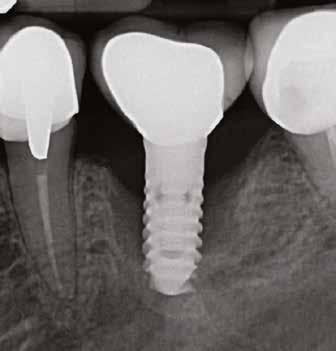

1. ábra: Dr. Jung 10 éves kontrollal rendelkező 4.7-es helyén levő Dentium short implantációja. Preoperativ CT, ínyformázó 4 hónappal a műtét után, valamint 4 hónap múlva 4.7-es szólókorona.

2. ábra: Dr. Park esete. 4.6-os fogon levő jelentős csontfelritkulás röntgenképe, extractio és iGBR alkalmazása Osteon Xenoval. 4 hónap múlva Dentium short implantátum, majd 4 hónap múlva korona készítése.

Prof. Jung Ui Won szöuli parodontológus a rövid implantátumok rizikómenedzselésével foglalkozott előadásában. Eseteket mutatott be 10 éves követéssel, ahol rendkívül alacsony csontkínálat mellett tudott sikeresen short megoldást találni.